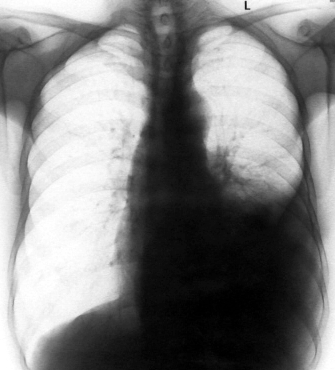

男,54岁,咳嗽,气喘半年,胸痛一月.

血性胸水

左侧胸腔积液 斜裂积液 心包积液 左肺不张 考虑左肺ca并胸膜心包转移。

支持左肺下叶中心型肺癌(累及舌叶)伴阻塞性肺炎、膨胀不全、胸腔积液、心包少量积液。

考虑左肺下叶中央型肺癌伴阻塞性肺炎及肺不张,纵隔受累可能,胸膜转移。